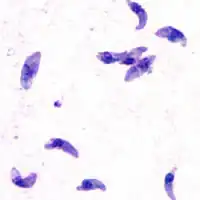

Giemsa stained T. gondii tachyzoites, 1000× magnification | |

Tachyzoites

Motile, and quickly multiplying, tachyzoites are responsible for expanding the population of the parasite in the host.[47][30]: 19 When a host consumes a tissue cyst (containing bradyzoites) or an oocyst (containing sporozoites), the bradyzoites or sporozoites stage-convert into tachyzoites upon infecting the intestinal epithelium of the host.[30]: 359 During the initial acute period of infection, tachyzoites spread throughout the body via the blood stream.[30]: 39–40 During the later, latent (chronic) stages of infection, tachyzoites stage-convert to bradyzoites to form tissue cysts. To survive in the host, tachyzoites manipulate the immune response by injecting the contents of rhoptries into host cells. This seems to be vital for their survival, as knock-out strains of T. gondii which are unable to inject hosts with rhoptries have been shown to be avirulent in vivo.[29]